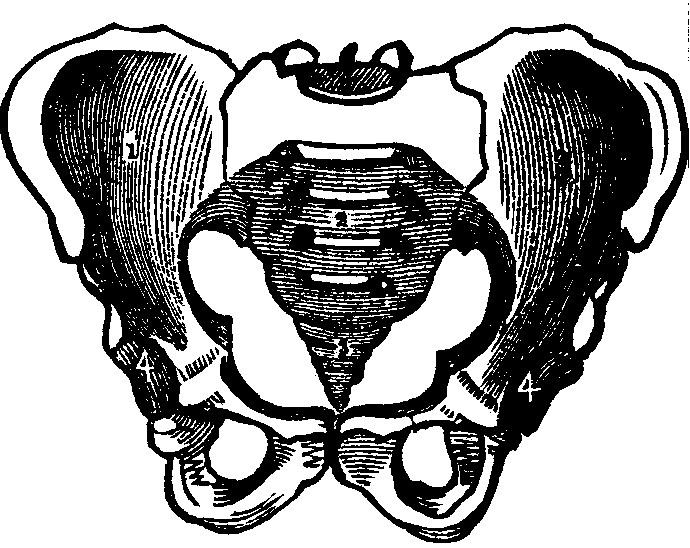

Fig. 15. A representation of the pelvic bones. e. The

lumbo-sacral joint. 2. The sacrum. 3. Coccyx. 1, 1. The

innominata. 4,4. Acetabula.

The Pelvis is an open bony structure, consisting of the Os

Innominata, one on either side, and the Sacrum and Coccyx behind. The

Sacrum, during childhood, consists of five bones, which in later

years unite to form one bone. It is light and spongy in texture, and the

upper surface articulates with the lowest vertebra, while it is united at

its inferior margin to the coccyx. The Coccyx is the terminal bone

of the spinal column. In infancy it is cartilaginous and composed of

several pieces, but in the adult these unite and form one bone. The

Innominata, or nameless bones, during youth, consist of three

separate pieces on each side; but as age advances they coalesce and form

one bone. A deep socket, called the acetabulum, is found near their

junction, which serves for the reception of the head of the thigh-bone.